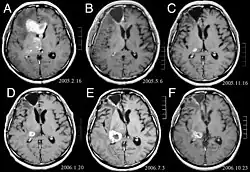

Bei Diagnose und Behandlung dieser Läsionen wurden in jüngster Zeit erhebliche Fortschritte erzielt, wodurch das Überleben und die Kontrolle der Symptomatik verbessert wurden. Das Auftreten von Anzeichen und Symptomen ähnelt denen anderer massiver Läsionen im Gehirn. Das Diagnoseverfahren der Wahl ist die Kernspintomographie unter Verwendung von Kontrastmitteln.

Die Literatur zeigt äquivalente Ergebnisse für Chirurgie und Radiochirurgie. Letzteres scheint bequemer, effektiver und sicherer für kleine Läsionen oder in Regionen zu sein, die für eine Operation nicht zugänglich sind. Die Radiochirurgie ist eine sinnvolle Alternative für Patienten, die aus medizinischen Gründen nicht operiert werden können. Die Operation ist jedoch eindeutig die optimale Methode, um Gewebe für die Diagnose zu erhalten und die Läsionen zu entfernen, die einen Masseneffekt verursachen. Daher sollten Radiochirurgie und Chirurgie besser als zwei komplementäre, aber unterschiedliche Methoden betrachtet werden, die je nach der unterschiedlichen Situation des Patienten angewendet werden.[44] Für fast 50 Prozent der Patienten mit einem oder zwei Hirnmetastasen kommt eine chirurgische Entfernung aufgrund der Unzugänglichkeit der Läsionen, der Ausdehnung der systemischen Erkrankung oder anderer Faktoren nicht in Frage. Diesen und anderen Patienten mit multiplen Metastasen wird normalerweise eine panenzephale Strahlentherapie als Standardbehandlung angeboten. Tatsächlich erreichen bis zu fast 50 Prozent von ihnen mit dieser Therapie eine Verbesserung der neurologischen Symptome und 50 bis 70 Prozent eine erkennbare Reaktion.[45][46][47] Bei Hirnmetastasen wird die Chemotherapie selten primär angewendet.

Bei den meisten Patienten mit Hirnmetastasen beträgt das mediane Überleben nur vier bis sechs Monate nach einer panenzephalen Strahlentherapie. Patienten unter 60 Jahren mit einzelnen Läsionen und einer kontrollierten systemischen Erkrankung können jedoch ein längeres Überleben erzielen, da sie einen aggressiveren Behandlungsansatz vertragen können.